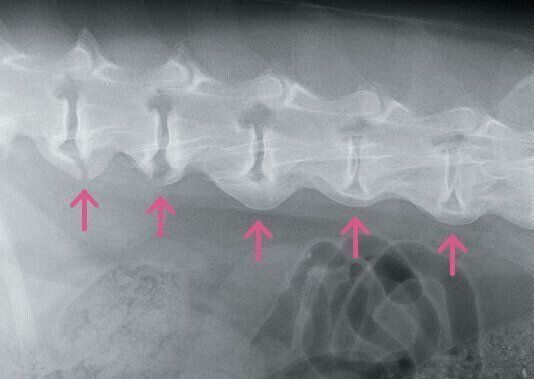

変形性脊椎症(へんけいせいせきついしょう)

主に加齢が原因で、背骨の間にある椎間板とその周辺の背骨が変形する病気です。隣り合う背骨同士が不安定になるとトゲのような骨ができてきて、最終的に背骨同士がくっついたような状態になります。シニア犬の半数近くが罹患しているという報告も。発症した背骨のまわりは寒さでこわばりやすく、急激に寒くなる晩秋~初冬は、より痛みを感じやすくなります。